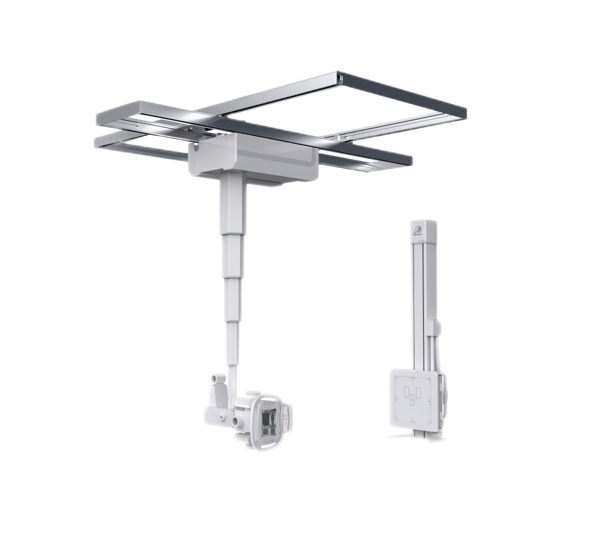

● 双向自动跟踪

探测器与球管双向自动跟踪,无需手动校正,多角度高精度实时同步;

胸片位、床上位电动转换,一键到位。

● 手动电动一体化

悬吊配备手动模式与电动模式,沿天轨横纵移动时可选手动或电动,满足不同医护人员使用习惯。